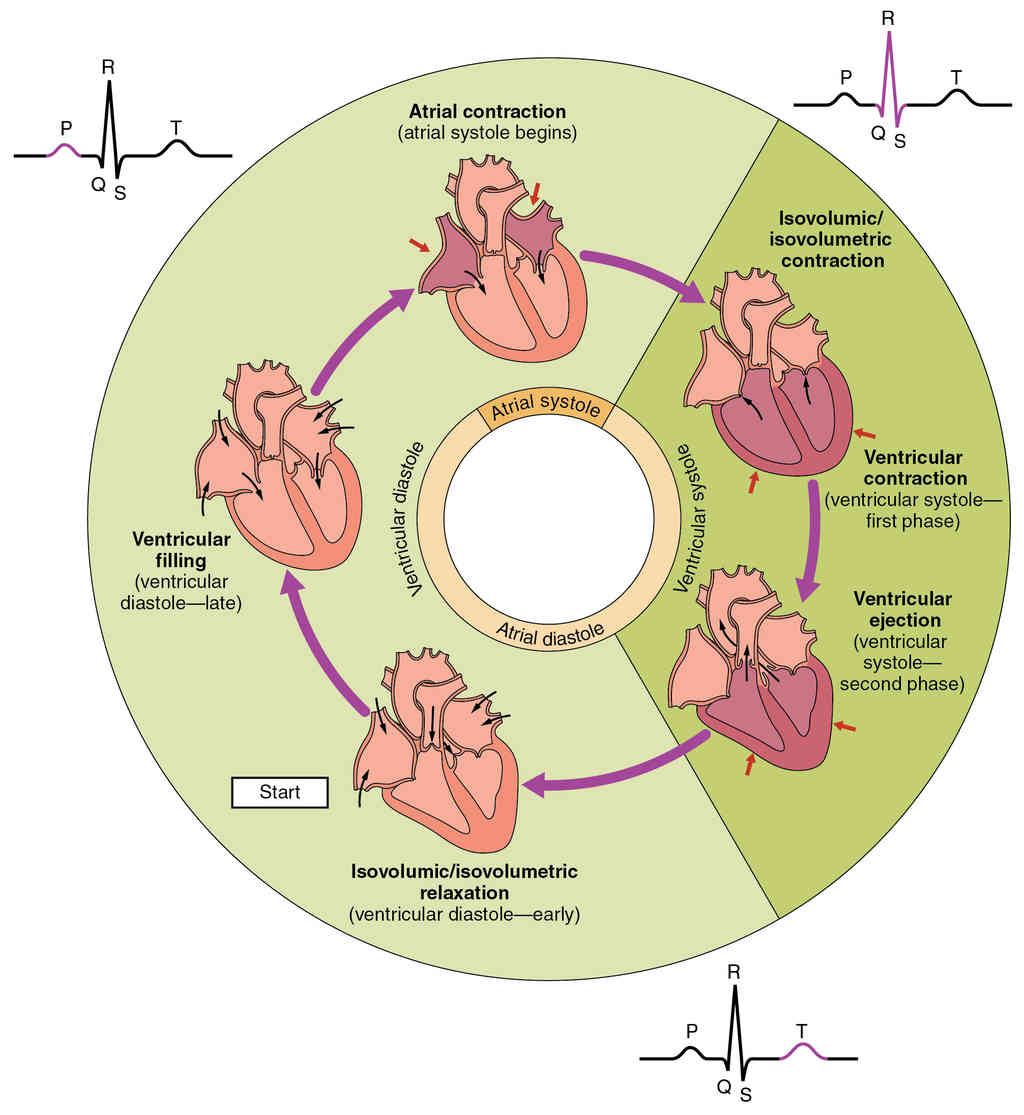

This page is under construction. For now, it is just a resource of the images found in the OpenStax Anatomy and Physiology Handbook. It wil slowly change into a revision tool. Each slide has a number. Use this to refer to the slide. When completed, it will have an unlabelled section, with labelled slides in parallel. On the unlabelled slides, write your answer and use the labelled slide to assess yourself. Keep track by also noting the number on each slide. Improvement at each attempt is important, more so than full marks on a first attempt.